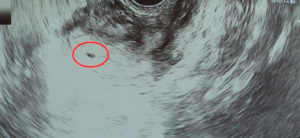

Ультразвуковое исследование и желтое тело

Можно ли заметить плодное яйцо на УЗИ на данном сроке? К сожалению, сейчас еще нет. Даже если проходить обследование влагалищным датчиком, так как оно еще очень маленького размера.

Доктор способен заметить только лишь хороший, пышный эндометрий, типичный для этой фазы месячного цикла, и желтоватое тело в яичнике.

А в некоторых случаях и 2 желтоватых тела, то есть в каждом яичнике по одному.

Что видно на фото плода?

Некоторые из них можно заметить на снимке УЗИ:

- предшественник эмбриона – доминантный фолликул, выглядит, как небольшойбугорок, хорошо заметный при исследовании ультразвуком;

- слизистая матки утолщается, это характерный признак увеличения количестваэстрогена, что бывает при беременности;

- хорошо видно желтое тело, сформировавшееся в месте прикрепления яйцеклетки.